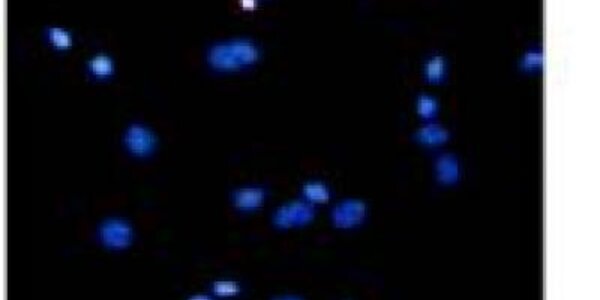

Study Finds Neuroprotective Effects Of Asiaticoside

Asiaticoside is the main saponin constituent of Centella asiatica, a plant long used in the Ayurvedic system of medicine that has become popular for human collagen synthesis applications, like anti-wrinkle treatments. In the central nervous system, Asiaticoside has been found by some studies to attenuate in vitro neuronal damage caused by exposure to β-amyloid. However, any potential neuroprotective properties in glutamate-induced excitotoxicity have not been fully studied.  Researchers from Fourth Military Medical University of Chinese PLA in China are now reporting that pretreatment…